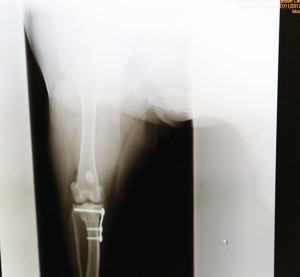

• Tibial Plateau Leveling Osteotomy TPLO

fracture-mending-tplo-580

• fracture-mending-tplo-580